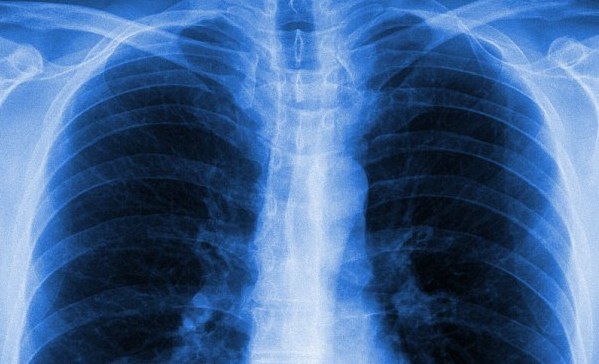

Члены авторитетной комиссии из консультационного комитета американского агентства по контролю над лекарственными препаратами одобрили новое средство, разработанное компанией Vertex. Препарат Orkambi, основанный на имеющейся версии Kalydeco, но с новой составляющей – Lumacaftor, предназначен для спасения пациентов с кистозным фиброзом. Данный недуг является наследственным и связан с мутацией в определенных генах. В результате, у пациента наблюдаются тяжелые нарушения органов дыхания, мокрота закупоривает легкие и делает их более уязвимыми к воздействию бактериальной микрофлоры. Именно в эту генетическую несправедливость, виновную в половине случаев развития муковисцидоза, и вносит коррективы новое средство.

В ходе клинических испытаний препарата его эффективность удалось подтвердить. Функция легких настолько улучшилась благодаря новому лечению, что эксперты из королевского университета Белфаста назвали терапию настоящим прорывом. Orkambi останавливает прогрессирование заболевания, позволяет пациентам постепенно вернуться к нормальной активной жизни, завести семью, выйти на работу и даже покинуть списки больных, ожидающих донорских легких.